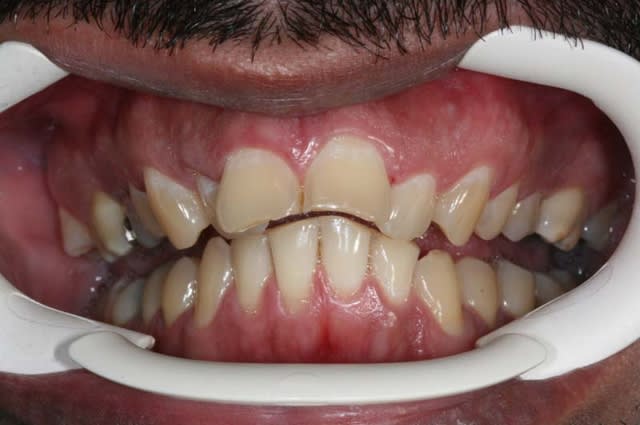

il ne peut plus croquer (mobilité des dents Sup.)

Il grince surtout sur les incisives centrales et latérales,

Pourtant les bruxomans ont généralement un parodonte qui s'adapté à cette pathologie, donc ce n'est pas ça qui devrait causer des mobilités...

C’est un fumeur? Il a une mobilité augmentée des incisives mais aucun signe d'inflammation. Peu de plaque et de tartre, peut être une parodontite agressive?

Prendre en charge le bruxisme (stress, habitudes nocives, médicaments (antidépresseurs tricycliques, dopaminergiques)?) -prise de conscience, alternative ttt médicamenteux en accord avc médecin traitant, sinon gouttières.